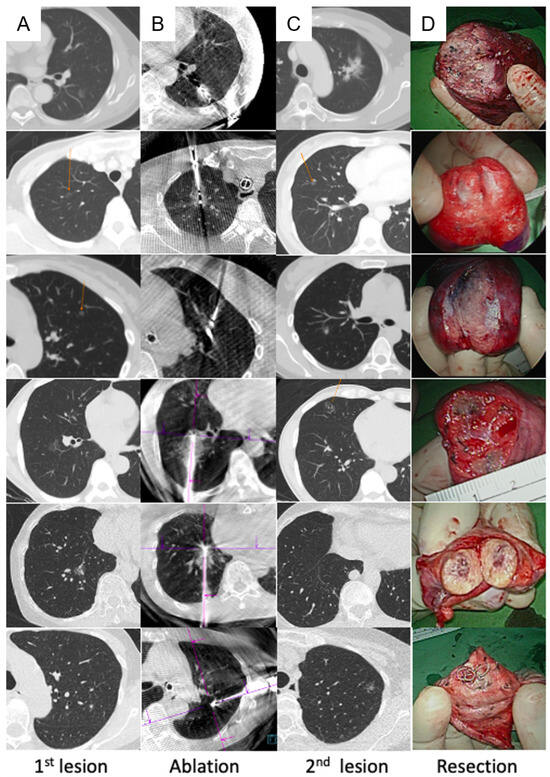

- Chang, L.K.; Yang, S.M.; Chung, W.Y.; Chen, L.C.; Chang, H.C.; Ho, M.C.; Chang, Y.C.; Yu, C.J. Cone-beam computed tomography image-guided percutaneous microwave ablation for lung nodules in a hybrid operating room: An initial experience. Eur. Radiol. 2024, 34, 3309–3319. [Google Scholar] [CrossRef]

- Chan, P.S.; Chang, L.K.; Malwade, S.; Chung, W.Y.; Yang, S.M. Cone beam CT derived laser-guided percutaneous lung ablation: Minimizing needle-related complications under general anesthesia with lung separation. Acad. Radiol. 2024; in press. [Google Scholar] [CrossRef]